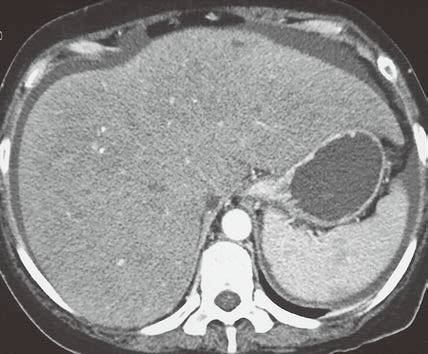

| 脂肪浸润(图1〜图 3) | 肝脏密度弥漫性减低。在肝脏脂肪变的低密度背景下,门静脉表现为高密度结构(平扫时正常门静脉呈低密度)。 | 由于三酰甘油过度沉积所致,见于肝硬化或其他肝脏疾病。正常肝脏平均CT值不低于脾脏,肝脏脂肪 浸润时CT密度较低。肝硬化引起脂肪浸润,伴有肝右叶萎缩,尾状叶体积增大。 |

图3肝硬化再生结节